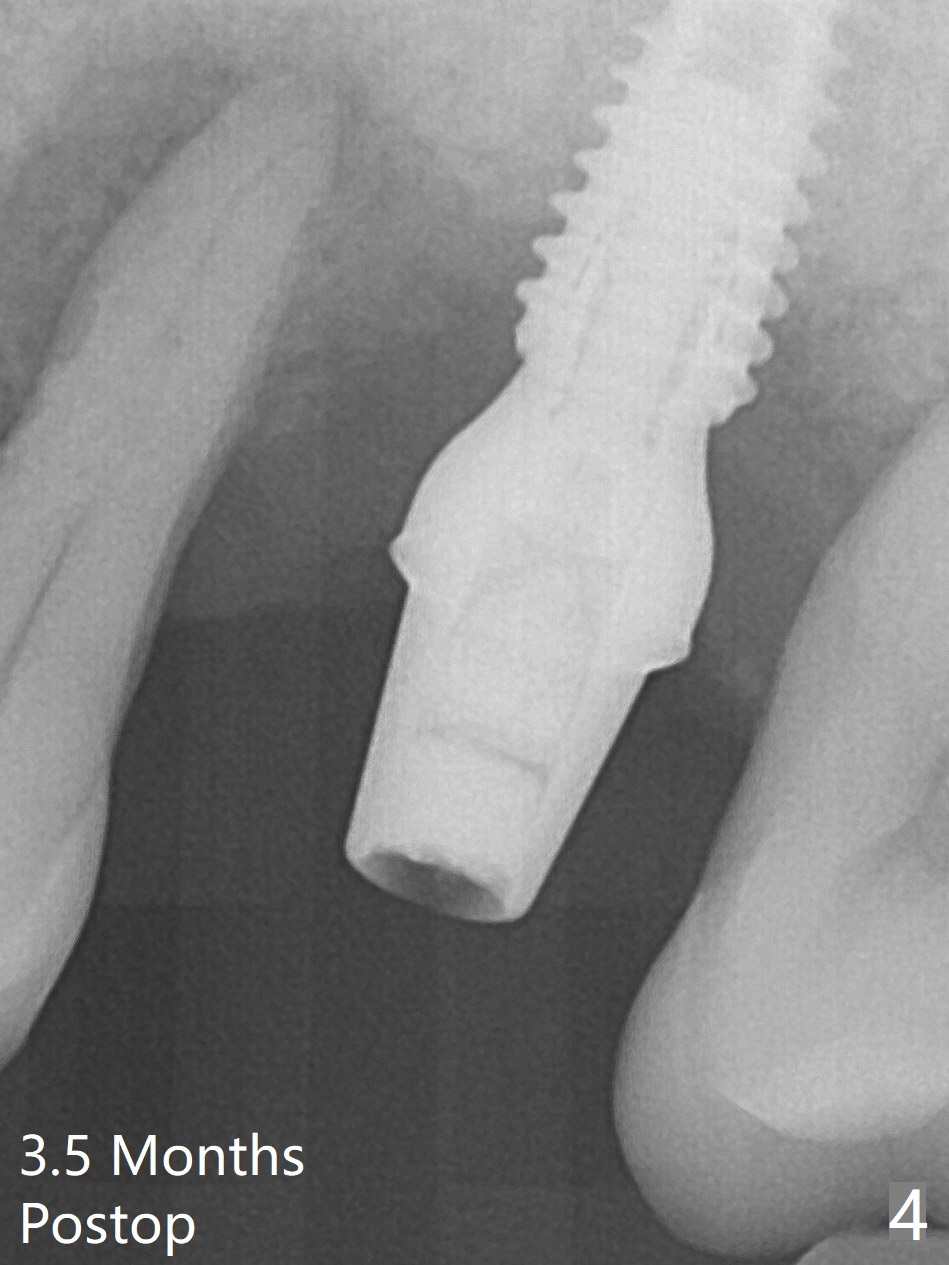

Bone height at #14 two months post exfoliation is ~ 4 mm (Fig.1). Bone expansion is difficult because of dense bone. After drilling, a 4.5 mm tap is inserted with stability (Fig.2). Sinus lift is accomplished with RT3 and autogenous bone prior to placement of a 4.5x8.5 mm implant (Fig.3). Because of flapless surgery and tight and long gingiva, bone graft around the coronal end of the implant is intentionally not placed. A 5.5x5(4) mm abutment is immediately placed for an immediate provisional. (Fig.4). Take PA and impression when the patient returns. The provisional dislodges 3.5 months postop (Fig.4); impression is taken. The patient reports hot sensitivity and pain after meal at the implant site (Fig.5). After removal of the implant crown/abutment, she feels better. If not, it seems necessary to extract the tooth #13 for a 13 mm long implant with a mill abutment (Fig.6).